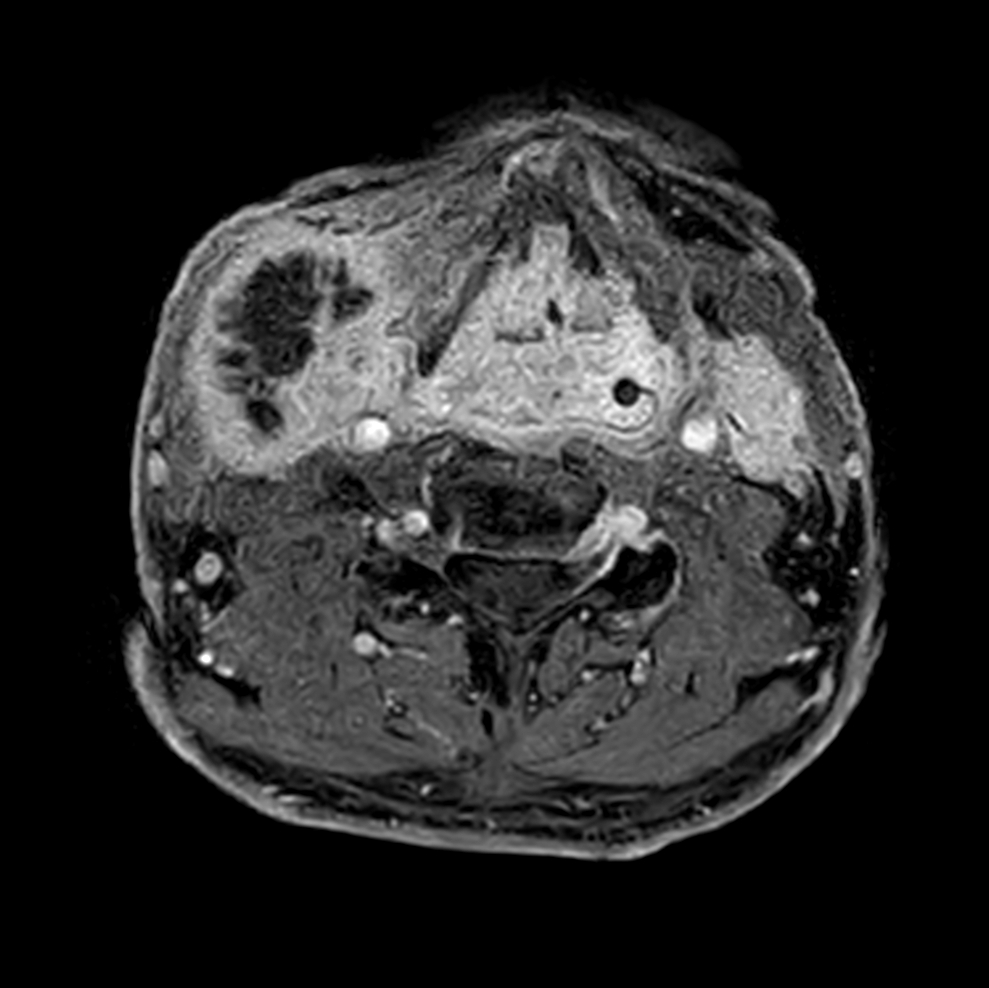

Axial T1w mDIXON XD - pre-gado

Axial T1w mDIXON XD - post-gado (dyn 1)

Axial T1w mDIXON XD - post-gado (dyn 6)